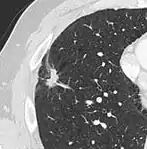

- Vascular convergence is where vessels converge to a nodule without adjoining or contacting the edge of the nodule, and is mainly seen in peripheral subsolid lung cancers.[9] It reflects angiogenesis.[9]

Air bronchograms is defined as a pattern of air-filled bronchi on a background of airless lung, and may be seen in both benign and malignant nodules, but certain patterns thereof may help in risk stratification.[9]